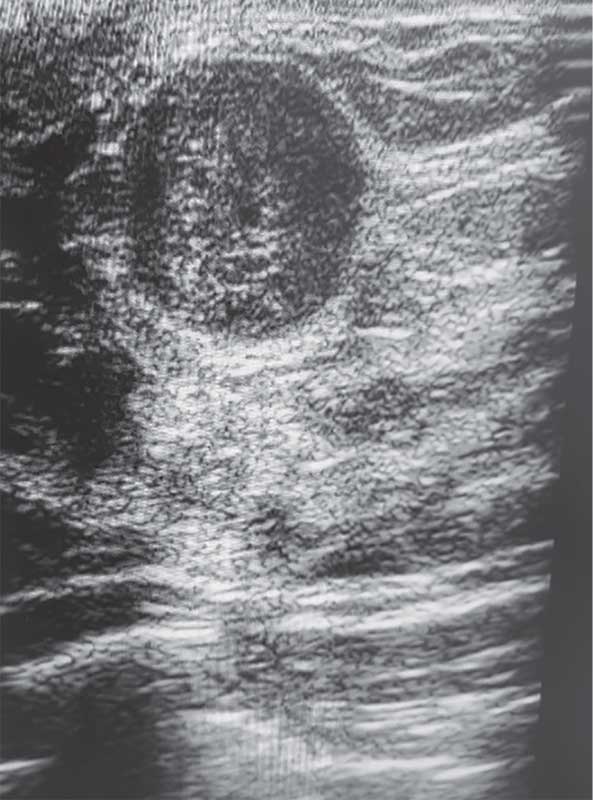

Рис. 1. Эхограмма правостороннего мастита у 12-летней девочки

Мастит – воспаление паренхимы и стромы МЖ, клинически проявляющееся локальной болезненностью и уплотнением, гиперемией кожи, лихорадкой и/или выделениями из соска [1, 9]. Существуют неонатальные, лактационные и нелактационные формы [1, 9]. В неонатальном периоде (до пяти недель жизни) мастит встречается у представителей обоего пола, нередко на фоне влияния материнских гормонов и вторичного инфицирования [1, 9]. Лактационный мастит связан с проникновением бактерий (чаще стафилококков и стрептококков) через трещины соска [1, 9]. В подростковом возрасте нелактационный мастит ассоциируют с инфекцией при эктазии протоков или метаплазии протокового эпителия [1, 9].

При УЗИ кожа и подкожно-жировая клетчатка утолщены, граница между слоями нечеткая, определяется гипоэхогенная зона отека, при цветовом дуплексном картировании кровоток усилен [5–7, 10]. У девочек при мастите часто лоцируются сложные кисты МЖ с гиперэхогенными перегородками, гипо- и анэхогенными участками внутри [5, 10]. При формировании абсцесса может визуализироваться гиперэхогенная капсула, внутри которой участок с гетерогенной структурой определяется только по периферии образования [5, 7, 10].

Эхографические признаки: утолщение кожи и гиподермы, размытость границы слоев, гипоэхогенный отек. При выполнении цветового допплеровского картирования (ЦДК) отмечается усиление кровотока [5–7, 10]. Иногда встречаются сложные кисты с перегородками и смешанной эхогенностью [5, 10]. Абсцесс визуализируется как образование с плотной гиперэхогенной капсулой и гетерогенным содержимым, васкуляризация – преимущественно по периферии (рис. 1) [5, 7, 10].